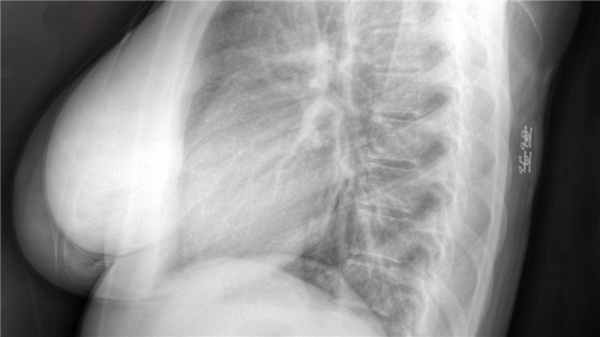

- Рентгенологическое обследование. В зависимости от локализации уплотнения, назначается снимок грудной клетки, брюшной полости, конечностей. Позволяет диагностировать образование, выявить его точное месторасположение, а также провести анализ состояния костных тканей и структур.

Рентгенография грудной клетки, конечностей или брюшной полости. Позволяет обнаружить образование, уточнить его расположение, рассчитать размер и оценить состояние окружающих тканей.